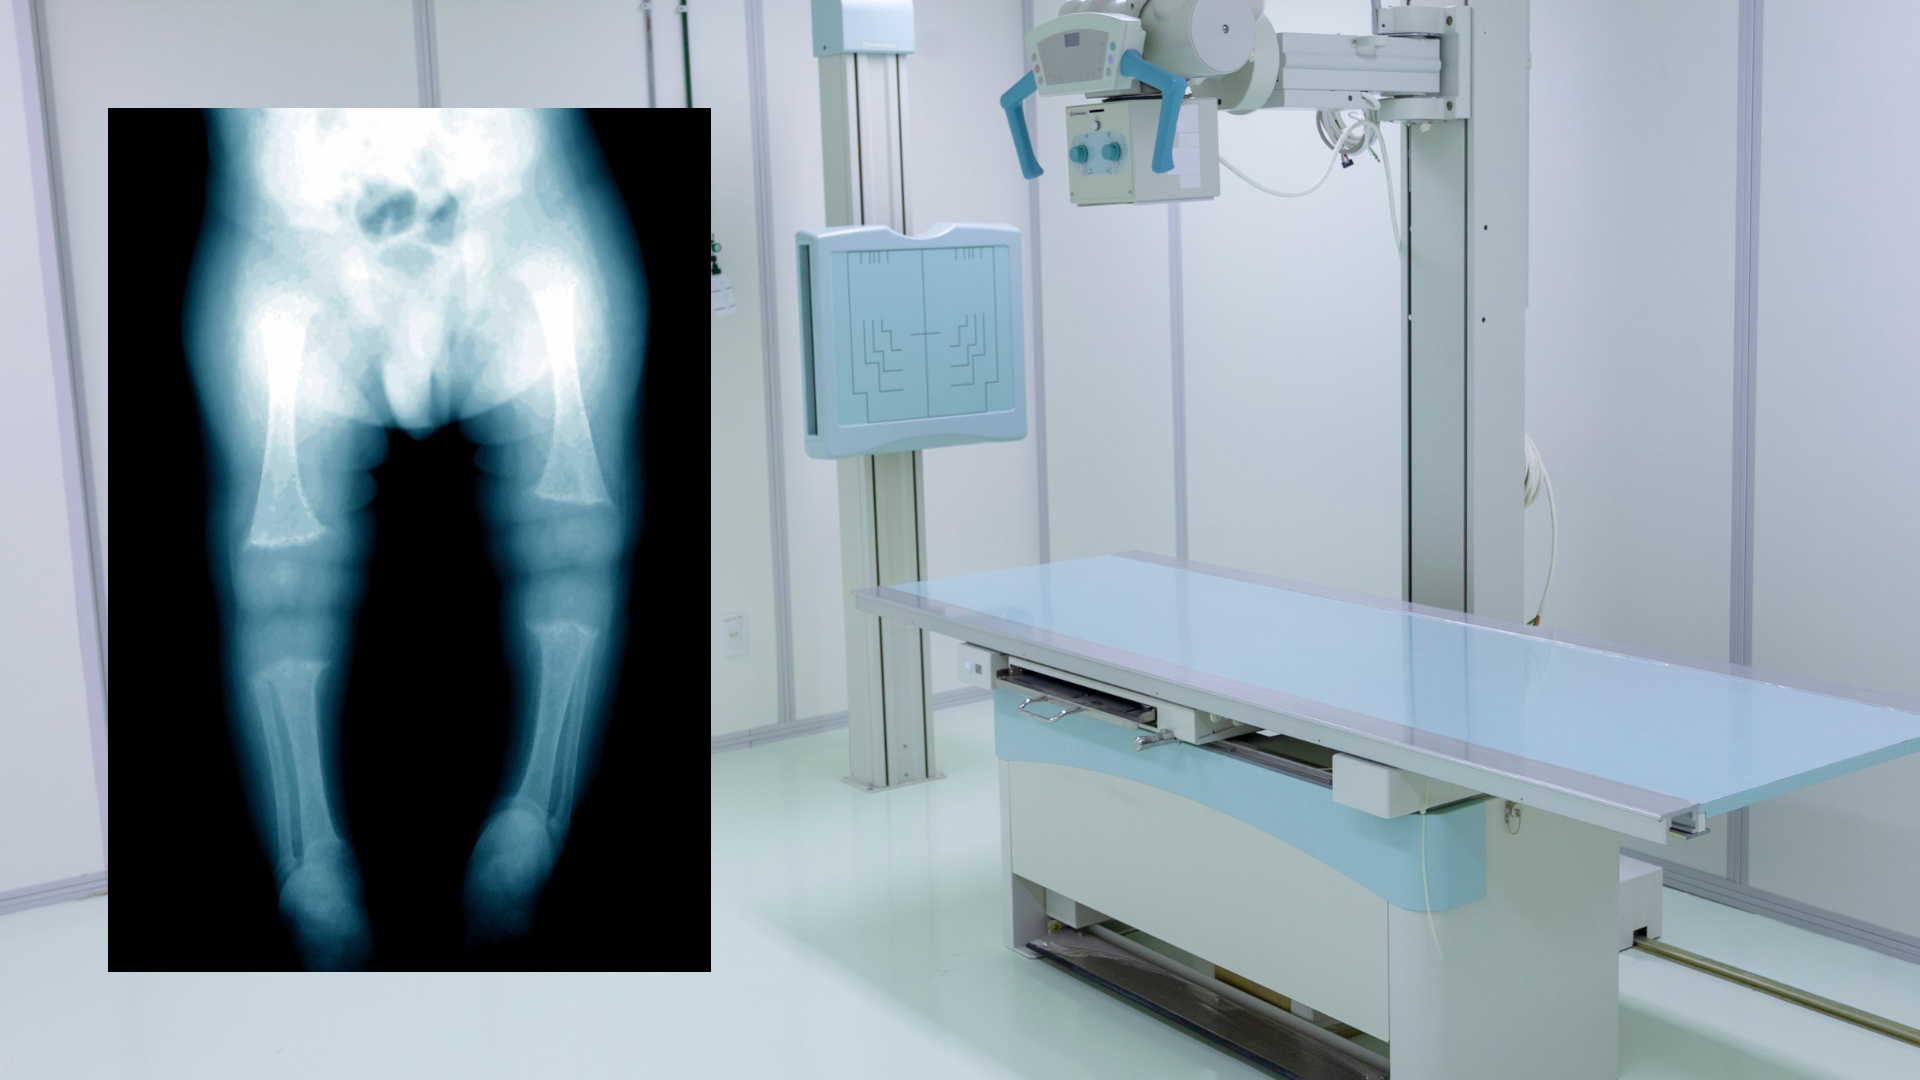

- Chụp X-quang xương dài để phát hiện dày sụn tăng trưởng và biến dạng xương.

- Biến dạng chi như chân vòng kiềng hoặc chân chữ X.